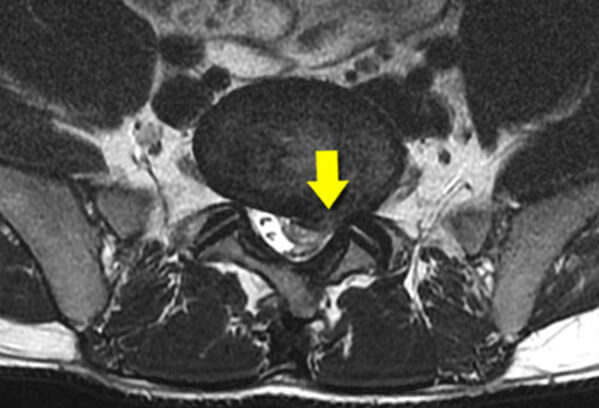

Dyskopatia – diagnoza i leczenie.

DYSKOPATIA – diagnoza i leczenie Jest to powszechnie występująca choroba kręgosłupa. Dotyka coraz częściej bardzo młodych ludzi. Jest…